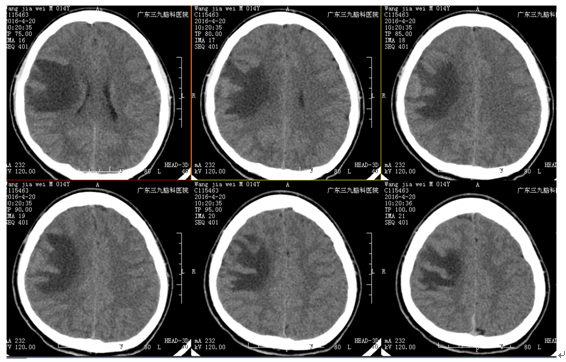

王某某,男,14岁,1年前发热及口角抽搐,在外院抗病毒、抗癫痫治疗,治疗效果不理想,近2周症状加重伴头晕头痛。外院MR:右额不规则异常强化(斑片状、环形强化),考虑感染性病变。既往外院实验室检查:脑脊液免疫球蛋白M0.357mg/L(0.000-0.300);脑脊液葡萄糖:3.54 mmol/L;氯117.2 mmol/L蛋白:0.42g/L;白细胞:8×10^6/L;单核细胞:8×10^6/L;入院完善MR:病灶和外院2015-8-27MR相比,病灶扩大。诊断:右额占位性病变(寄生虫?)

治疗:患者全麻下行右额占位性切除术,术程顺利,术中右额中央前回前方多囊性占位,皮层表面粘连,囊性占位下方与脑组织边界尚清晰,切开囊壁可见中央脓性液体。术中冰冻提示肉芽肿,病理:符合慢性脑脓肿并肉芽肿形成。PAS及GMS染色查见个别真菌孢子,形态较符合着色芽孢菌。诊断:颅内炎性肉芽肿。